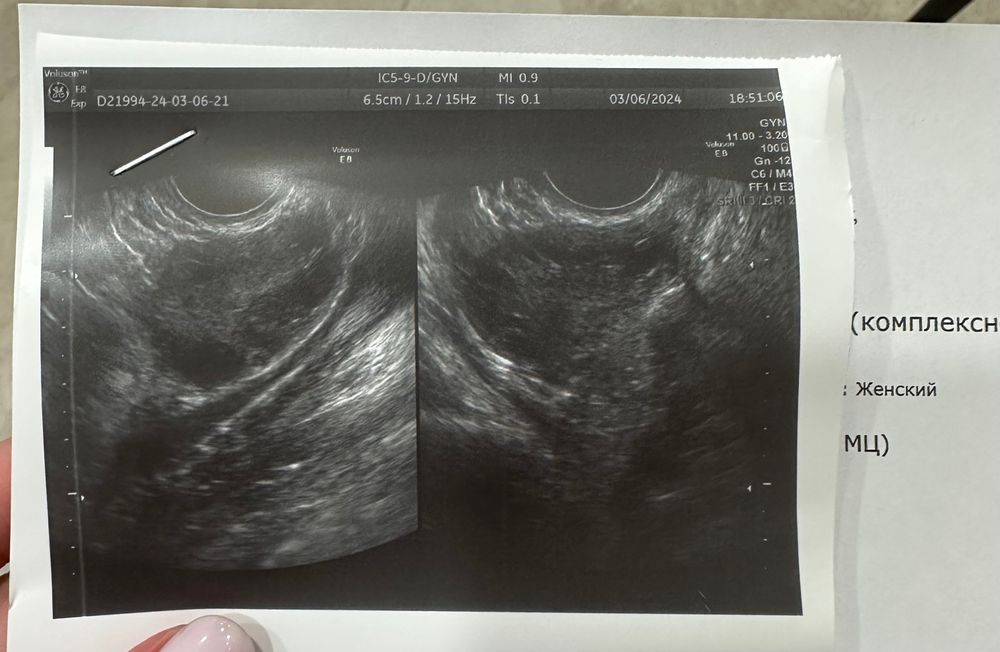

ФолликулометрияДевочки, подскажите было у кого-то такое? Была на узи 1.03, сказали жт есть (1 фото)

Пошла второй раз на узи 6.03, но в другую клинику и врачу, жт нет…(второе фото) куда оно делось? Может его просто не увидели?